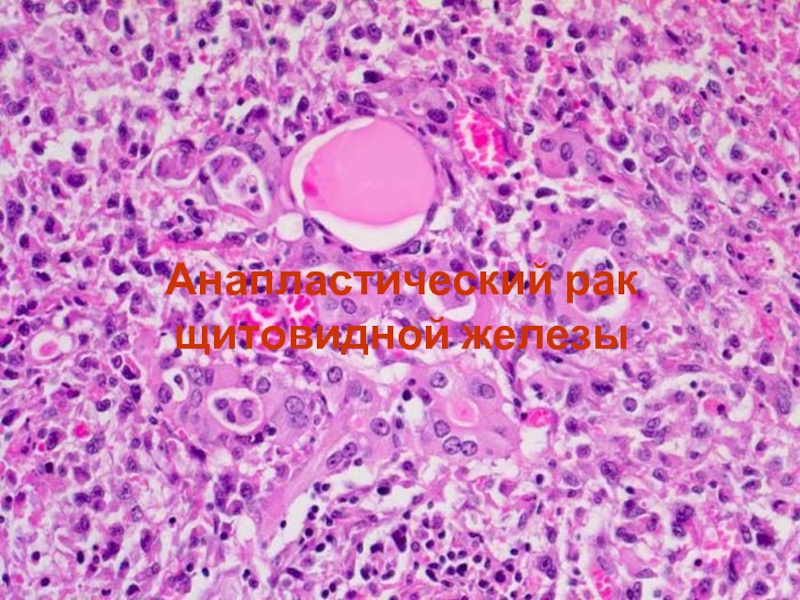

Фотографии опухоли медуллярной аденокарциномы